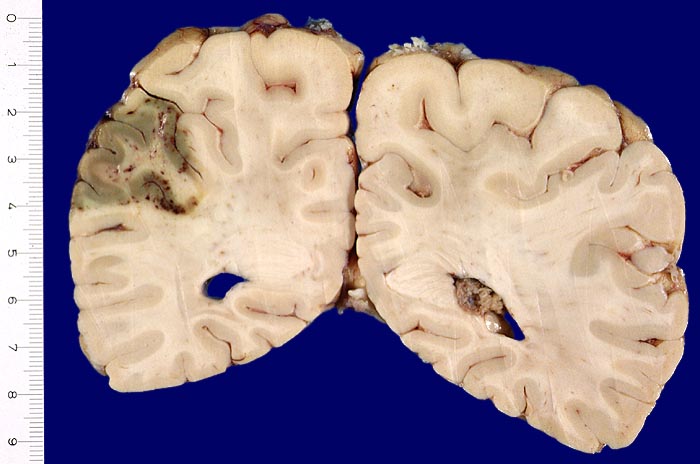

PathoPic – image database / PathoPic ID 3187 - Frischere anämische Enzephalomalazie mit sekundären Einblutungen

Frischere anämische Enzephalomalazie mit sekundären Einblutungen

Frische Enzephalomalazie occipito-parietal links (8x3x3cm) im peripheren Versorgungsgebiet der A. cerebri media links. Grauverfärbung der Hirnrinde im Infarktareal und punktförmige dunkelrote Einblutungen.

Rezidivierter Myokardinfarkt mit Fibrinthrombus in der linken Herzkammer und Morbus embolicus.